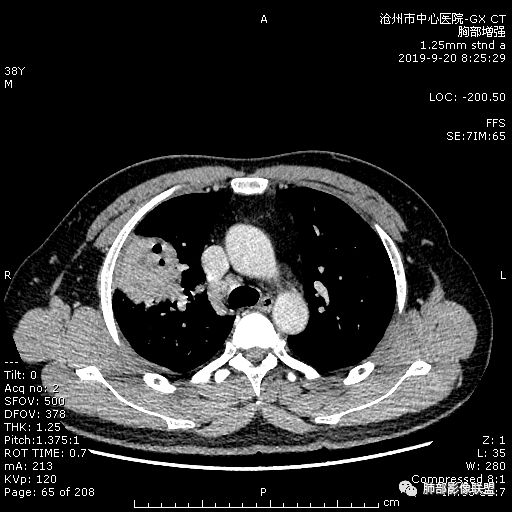

青年男性,肿瘤指标无异,右上中肺团片影,形态不规,跨叶生长,

病灶内见坏死,增强边缘强化,考虑炎性肉芽肿,TB,鉴别鳞。

年轻男性,咳嗽2月,痰中带血,胸痛,炎症指标稍高,肿标正常。影像,右肺上叶不规则团块影,浅分叶,伴边界不清磨玻璃影,从外周向内分布,局部胸膜增厚,病灶中央坏死,坏死边界尚清,空洞形成,空洞内壁光滑;考虑炎性肉芽肿性病变,结核可能,鉴别恶性肿瘤及真菌感染。病灶分布特点不考虑隐球。

右肺上叶不规则病灶,密度不均,有分叶,边缘不清,中央有坏死,坏死壁尚光滑,增强壁有强化,病灶有外朝内,整体收缩为主,慢性病程,考虑炎性病变,肺脓肿或者结核,淋巴结肿大,支气管截断,胸膜脂肪间隙变窄,加个鉴别恶性肿瘤。

38岁,男性,慢性咳嗽2月,右胸痛8天,无发热;白细胞高,肿瘤标志物不高;右上肺不规则块状影,周围有磨玻璃影,边界清,整体有膨胀感,分叶,与胸膜糊墙,并见栽赃,增强肿块中央坏死,周边强化。综合考虑,考虑恶性,鳞癌可能。

38岁,男性,慢性咳嗽2月,右胸痛8天,无发热。白细胞高,肿瘤标志物不高。右上肺不规则块状影,周围有磨玻璃影,边界模糊,整体有膨胀感,分叶,与胸膜糊墙,可疑栽赃,增强肿块中央坏死,边界清,周边强化明显,强化区有低密度影,壁不规则,跨叶生长,支气管截断,伴支气管扩张,综合考虑腺癌

中年男性,咳嗽2月,伴胸痛8天,少许痰血,无发热中性粒明显增高,低氧,肿标不高,右肺上叶不规则实性肿块,深分叶,局部凹陷呈月牙铲改变,多坏死,多空泡,前段支气管分支似见堵塞,2R、4R、10R和7区淋巴结肿大。考虑肺癌可能,建议支气管镜活检

晨读病例,右肺上叶胸壁处占位,边缘分叶毛刺,收缩力强,多发坏死,远端支气管截断,不均匀性强化,血管穿行变窄,纵隔多发淋巴结肿大,考虑恶性肿瘤,首先考虑腺癌

首先病灶示:跨尖、后、前三段,局部突入中叶;大家理解一下:是不是光滑的地方有叶裂,毛糙的地方没叶裂。

周围GGO,不是远端;

而且这个病灶明显跨段,属于外围的病变,不受某一段支气管的局限;

宽基底,胸膜增厚

但是深分叶,坏死部分内壁不清

近端支气管堵塞

肺门淋巴结肿大